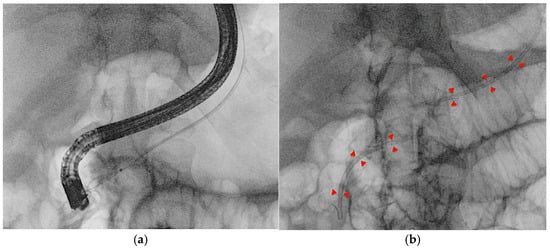

4.2. EUS–Pancreatic Drainage (EUS-PD)

Two main approaches for EUS-PD exist: EUS-Rv, where a small-caliber wire is advanced in an antegrade manner into the duodenum for ERCP stenting (Figure 8), and EUS-PD transmural drainage, involving serial dilation and stent placement from the stomach or the duodenum (pancreaticogastrostomy/pancreaticoduodenostomy) [50]. Successful EUS-PD relies on precise pancreatic duct puncture and effective guidewire manipulation, given the small duct size, side branches, and potential strictures. A 19-gauge needle with a sharp tip and a 0.025-inch flexible-tip guidewire is generally recommended [51]. In cases with a small pancreatic duct, a 22-gauge needle combined with a smaller (0.018-or 0.021-inch) guidewire may be used, though these thinner guidewires can be challenging to manipulate even after successful duct puncture [52]. The advantage of the 22-gauge needle lies in its ability to puncture even a fibrotic pancreas or a stiff, narrow MPD; in their single-center retrospective study, Matsunami et al. reported high technical success in EUS-PD using a 22-gauge needle despite targeting a small MPD (median diameter 3.5 mm, range 1–14 mm) [53]. However, due to the limited fluoroscopic visibility and insufficient shaft stiffness for therapeutic device support that 0.018- and 0.021-inch guidewires typically offer, when initial access is achieved with a smaller guidewire, a subsequent exchange to a larger-caliber (0.025- or 0.035-inch), stiffer wire is often necessary to ensure procedural success [54]. Studies such as those by Inoue et al. [55] and Sasaki et al. [56] have noted the value of an ultra-tapered or hybrid wire with a stiff body to facilitate pushability and a soft tip to minimize ductal trauma. For patients with surgically altered anatomy, such as those who have undergone gastrectomy, selecting an appropriate puncture site can be difficult due to the reduced stomach volume. In such cases, transjejunal EUS-PD is an ideal approach, as the jejunum and pancreatic duct are closely anastomosed. A stiff guidewire, typically used for endoscopic long intestinal tube insertion, helps optimize this technique. After straightening the twisted afferent jejunal loop using an enteroscope, the guidewire is placed to maintain the loop’s shape. Additionally, by deploying the guidewire into the working channel of a forward-viewing echoendoscope (ropeway method), smooth scope insertion is achieved, facilitating the transjejunal EUS-PD procedure [57].

Figure 8. Radiological image of the EUS-PD rendezvous technique. (a) After placing a stent across pancreaticogastrostomy, the guidewire is advanced in an antegrade manner into the pancreatic duct under EUS guidance, followed by standard ERCP and transpapillary stent placement over the wire for pancreatic duct drainage. (b) The end of the procedure with the two stents (highlighted by the red arrows) in the main pancreatic duct.